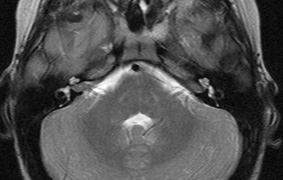

1. Schwannomas most commonly affect the fifth cranial nerve (CN), but any cranial nerve may be affected. In contrast to vestibular schwannomas (CN VIII), these typically do not grow large.84,90 Vestibular schwannomas (acoustic neuromas) are the classic finding in NF2 (Fig. 7). The risk for malignant transformation is low, but may be higher with radiation exposure.84,94

3. Other tumors: low-grade ependymomas and gliomas may affect the cervical spine and Brainstem (Fig. 7).84

Fig. 7. Neurofibromatosis type 2: Images of a 12-year-old boy with deafness and weakness in his arms and legs, whose father has bilateral deafness. Axial T2-weighted (a) and postcontrast axial (b) T2-weighted images reveal bilateral vestibular schwannomas, which are also known as acoustic neuromas (arrows). This is the classic finding of NF2. (b, c) Bilateral schwannomas are seen in Meckel's cave (arrowheads) and a (d) lower left cranial nerve schwannoma extends into the pars nervosa of the jugular foramen (arrow). (e) A part cystic and part solid enhancing ependymoma in seen within the cervical cord and medulla and within the distal cord and conus. (e, f) Thoracic schwannomas are present at numerous levels (arrowheads). Marked enhancement and thickening of the roots within the cauda equina also represent multiple schwannomas.